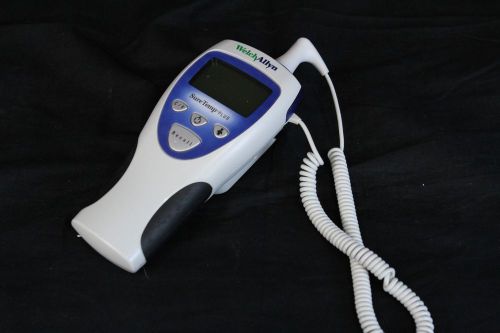

Welch Allyn Suretemp Plus 692 Oral Thermometer